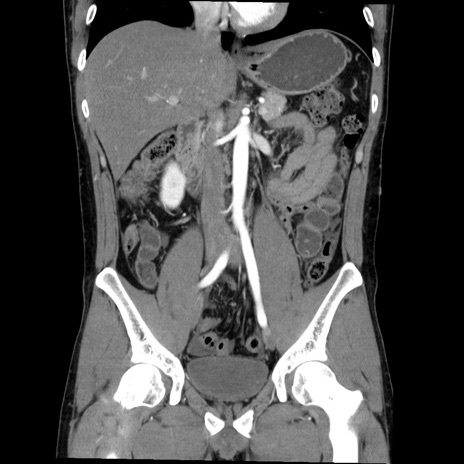

症例36(冠状断像)

【症例】20歳代 男性

【主訴】心窩部痛

【現病歴】今朝より上腹部痛あり。一旦軽快していたが再度出現したため救急要請。昨日夕に白身の魚を含む刺身を食べた。

【身体所見】BP 136/89mmHg、HR 74/min、BT 37.0℃、腹部:膨満、軟、心窩部に圧痛あり。反跳痛なし、筋性防御なし、腸雑音やや亢進あり。

【データ】WBC 17700、CRP 0.48